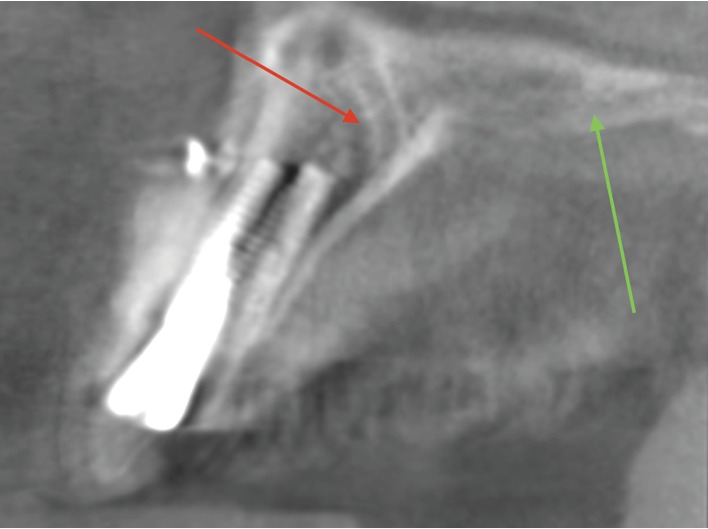

Послеоперационная КЛКТ была выполнена на том же оборудовании. При тщательном сравнении КЛКТ до и после имплантации был выявлен канал canalis sinuosus (CS) диаметром 2,3 мм, от которого отходили две мелкие ветви. Одна из них располагалась ближе к нёбной стороне и имела диаметр 1,9 мм, вторая находилась ближе к вестибулярной поверхности в области верхнего левого латерального резца/имплантата и имела диаметр 0,7 мм в самой корональной точке. Обе ветви относились к области латерального резца согласно классификации de Oliveira-Santos и соавт.

Послеоперационная КЛКТ, сагиттальная проекция в области левого верхнего резца. Дентальный имплант установлен. Диагностика затруднена наличием артефактов, вызванных титановым имплантатом; однако визуализируется большая небная ветвь КС (красная стрелка). Также визуализируются костные контуры левой большой небной артерии и нерва (зеленая стрелка).

Кроме того, костные контуры левой большой нёбной артерии и нерва были отчётливо видны на КЛКТ в переднем отделе верхней челюсти на расстоянии 10,1 мм от имплантата, что исключает их повреждение. Также по данным КЛКТ, расстояние от имплантата до резцового отверстия составляло 5,62 мм, а до резцового канала (canalis nasopalatinus) — 5,66 мм, что также исключает вмешательство в данные анатомические структуры.

Хотя КЛКТ обеспечивает точные трёхмерные изображения твёрдых тканей челюстно-лицевой области, у метода есть ограничения — артефакты изображения, возникающие из-за отклонений между реконструированной картинкой и реальным содержимым объекта. Имплантат — это высокоплотная структура, вызывающая артефакты лучевой жёсткости. Именно поэтому, при подозрении на повреждение CS по послеоперационной КЛКТ, было принято решение повторно оценить предоперационные снимки — без искажений от металла — для более точной диагностики.